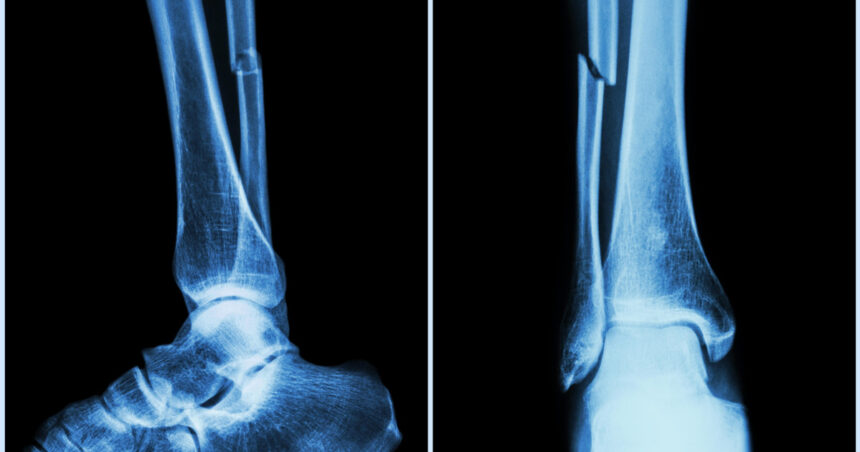

Fracturi vindecate în câteva minute: un lipici pentru oase, soluția găsită de cercetătorii chinezi

Cercetătorii chinezi au dezvoltat un adeziv osos inovator, denumit „Bone-02”, care poate trata fracturile și fragmentele osoase zdrobite în doar trei minute. Echipa de cercetare din provincia Zhejiang, condusă de dr. Lin Xianfeng de la spitalul Sir Run Run Shaw, a anunțat că această soluție medicală ar putea revoluționa modul în care sunt tratate fracturile.

Adezivul funcționează printr-un mecanism inspirat de modul în care stridiile aderă la suprafețe sub apă, reușind o fixare precisă chiar și în medii bogate în sânge, cum ar fi cele întâlnite în timpul intervențiilor chirurgicale. Un avantaj major al „Bone-02” este faptul că acesta se absoarbe natural în organism pe măsură ce osul se vindecă, eliminând necesitatea unei a doua operații pentru îndepărtarea implanturilor.

În testele efectuate, adezivul a demonstrat atât siguranță, cât și eficacitate, fiind utilizat cu succes la peste 150 de pacienți. Forța de lipire a oaselor a depășit 180 de kilograme, sugerând că ar putea înlocui implanturile metalice tradiționale în viitor. În plus, metoda ar putea reduce riscurile de reacții adverse și infecții post-operatorii.

Deși pe piață există deja diverse tipuri de cimenturi osoase, „Bone-02” se distinge prin proprietățile sale adezive reale. Rezultatele actuale sugerează că acest adeziv ar putea reprezenta un pas important spre un tratament mai rapid și mai sigur al fracturilor. Autoritățile sanitare chineze au aprobat dezvoltarea și aplicarea clinică a acestuia, cu planuri de a-l introduce în spitalele din țară ca alternativă standard la chirurgia ortopedică tradițională.